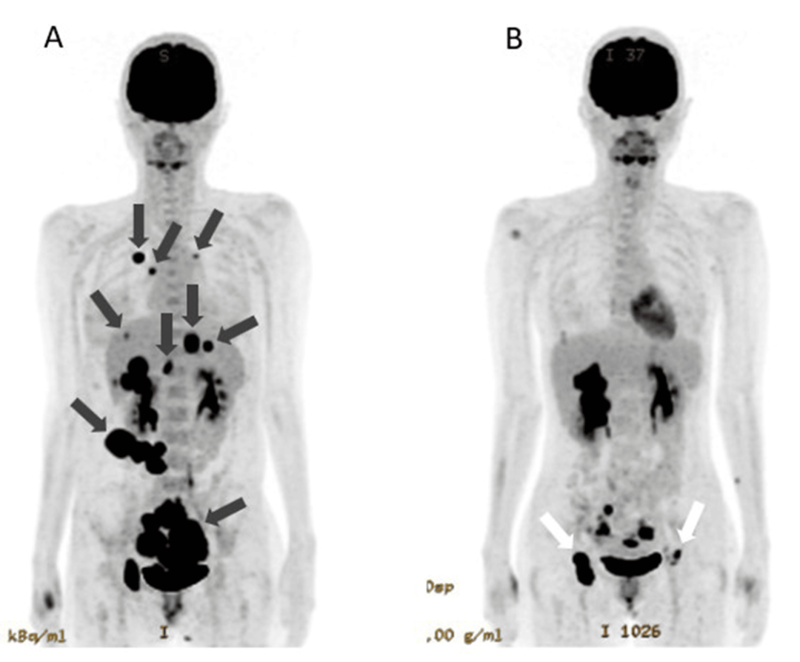

2024 年3 月《Cureus》期刊报道了一则IV期卵巢癌案例:一位 30 多岁的女性患者确诊时已出现双侧卵巢癌伴腹膜播散,同时存在肝、肺、骨多处转移,腹部有大量腹水,未接受手术和放疗,初始采用紫杉醇联合卡铂化疗方案。

治疗中,患者同步进行免疫治疗:从第18天起每两周注射 WT1-DC疫苗和纳武利尤单抗,通过红斑反应评估显示免疫激活良好。但因第 37 天腹水仍明显且 NK 细胞活性低,后续加入 NK 细胞治疗。

在第39、52、60天注射成熟NK细胞后,患者每次治疗后都出现高热,这是免疫系统被激活的信号。

第三次治疗后CEA、CA125指标明显下降,腹围减小,肝转移灶缩小。后续追加两次NK细胞治疗,142天后,PET-CT显示肺转移和腹膜播散消失,原发病灶显著缩小,患者计划进行根治性手术。治疗期间除发热外无其他副作用。